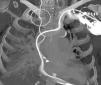

Mujer de 86 años, que ingresa en la unidad de cuidados intensivos con un bloqueo auriculoventricular de tercer grado, con inestabilidad hemodinámica y deterioro del nivel de conciencia. Se le inserta un catéter de estimulación cardiaca temporal con balón guiado mediante monitorización electrocardiográfica en espera de poder implantar un marcapasos definitivo. Tras el implante del mismo, se comenzó a retirar el catéter de estimulación cardiaca transitoria apreciándose la formación de un nudo (fig. 1). Mediante control fluoroscópico y apoyándose en el introductor, se apretó el nudo. Luego se retiró el introductor y, por último, se extrajo el catéter mediante tracción (fig. 2). No se ocasionaron lesiones vasculares ni otras complicaciones.